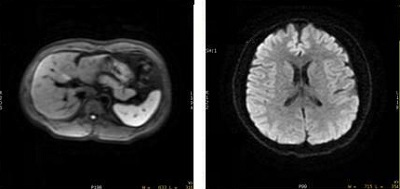

Figure 3. DWI breast images

Table 3. Image legend

NumberDescription

1PSD = DWI

Imaging Option = IR Prepared

User CV Enhanced fat suppression = 0 (off)

Note: the chemical shift artifact.

2PSD = DWI

User CV Enhanced fat suppression = 1 (on)

3PSD = DWI

Imaging Option = None